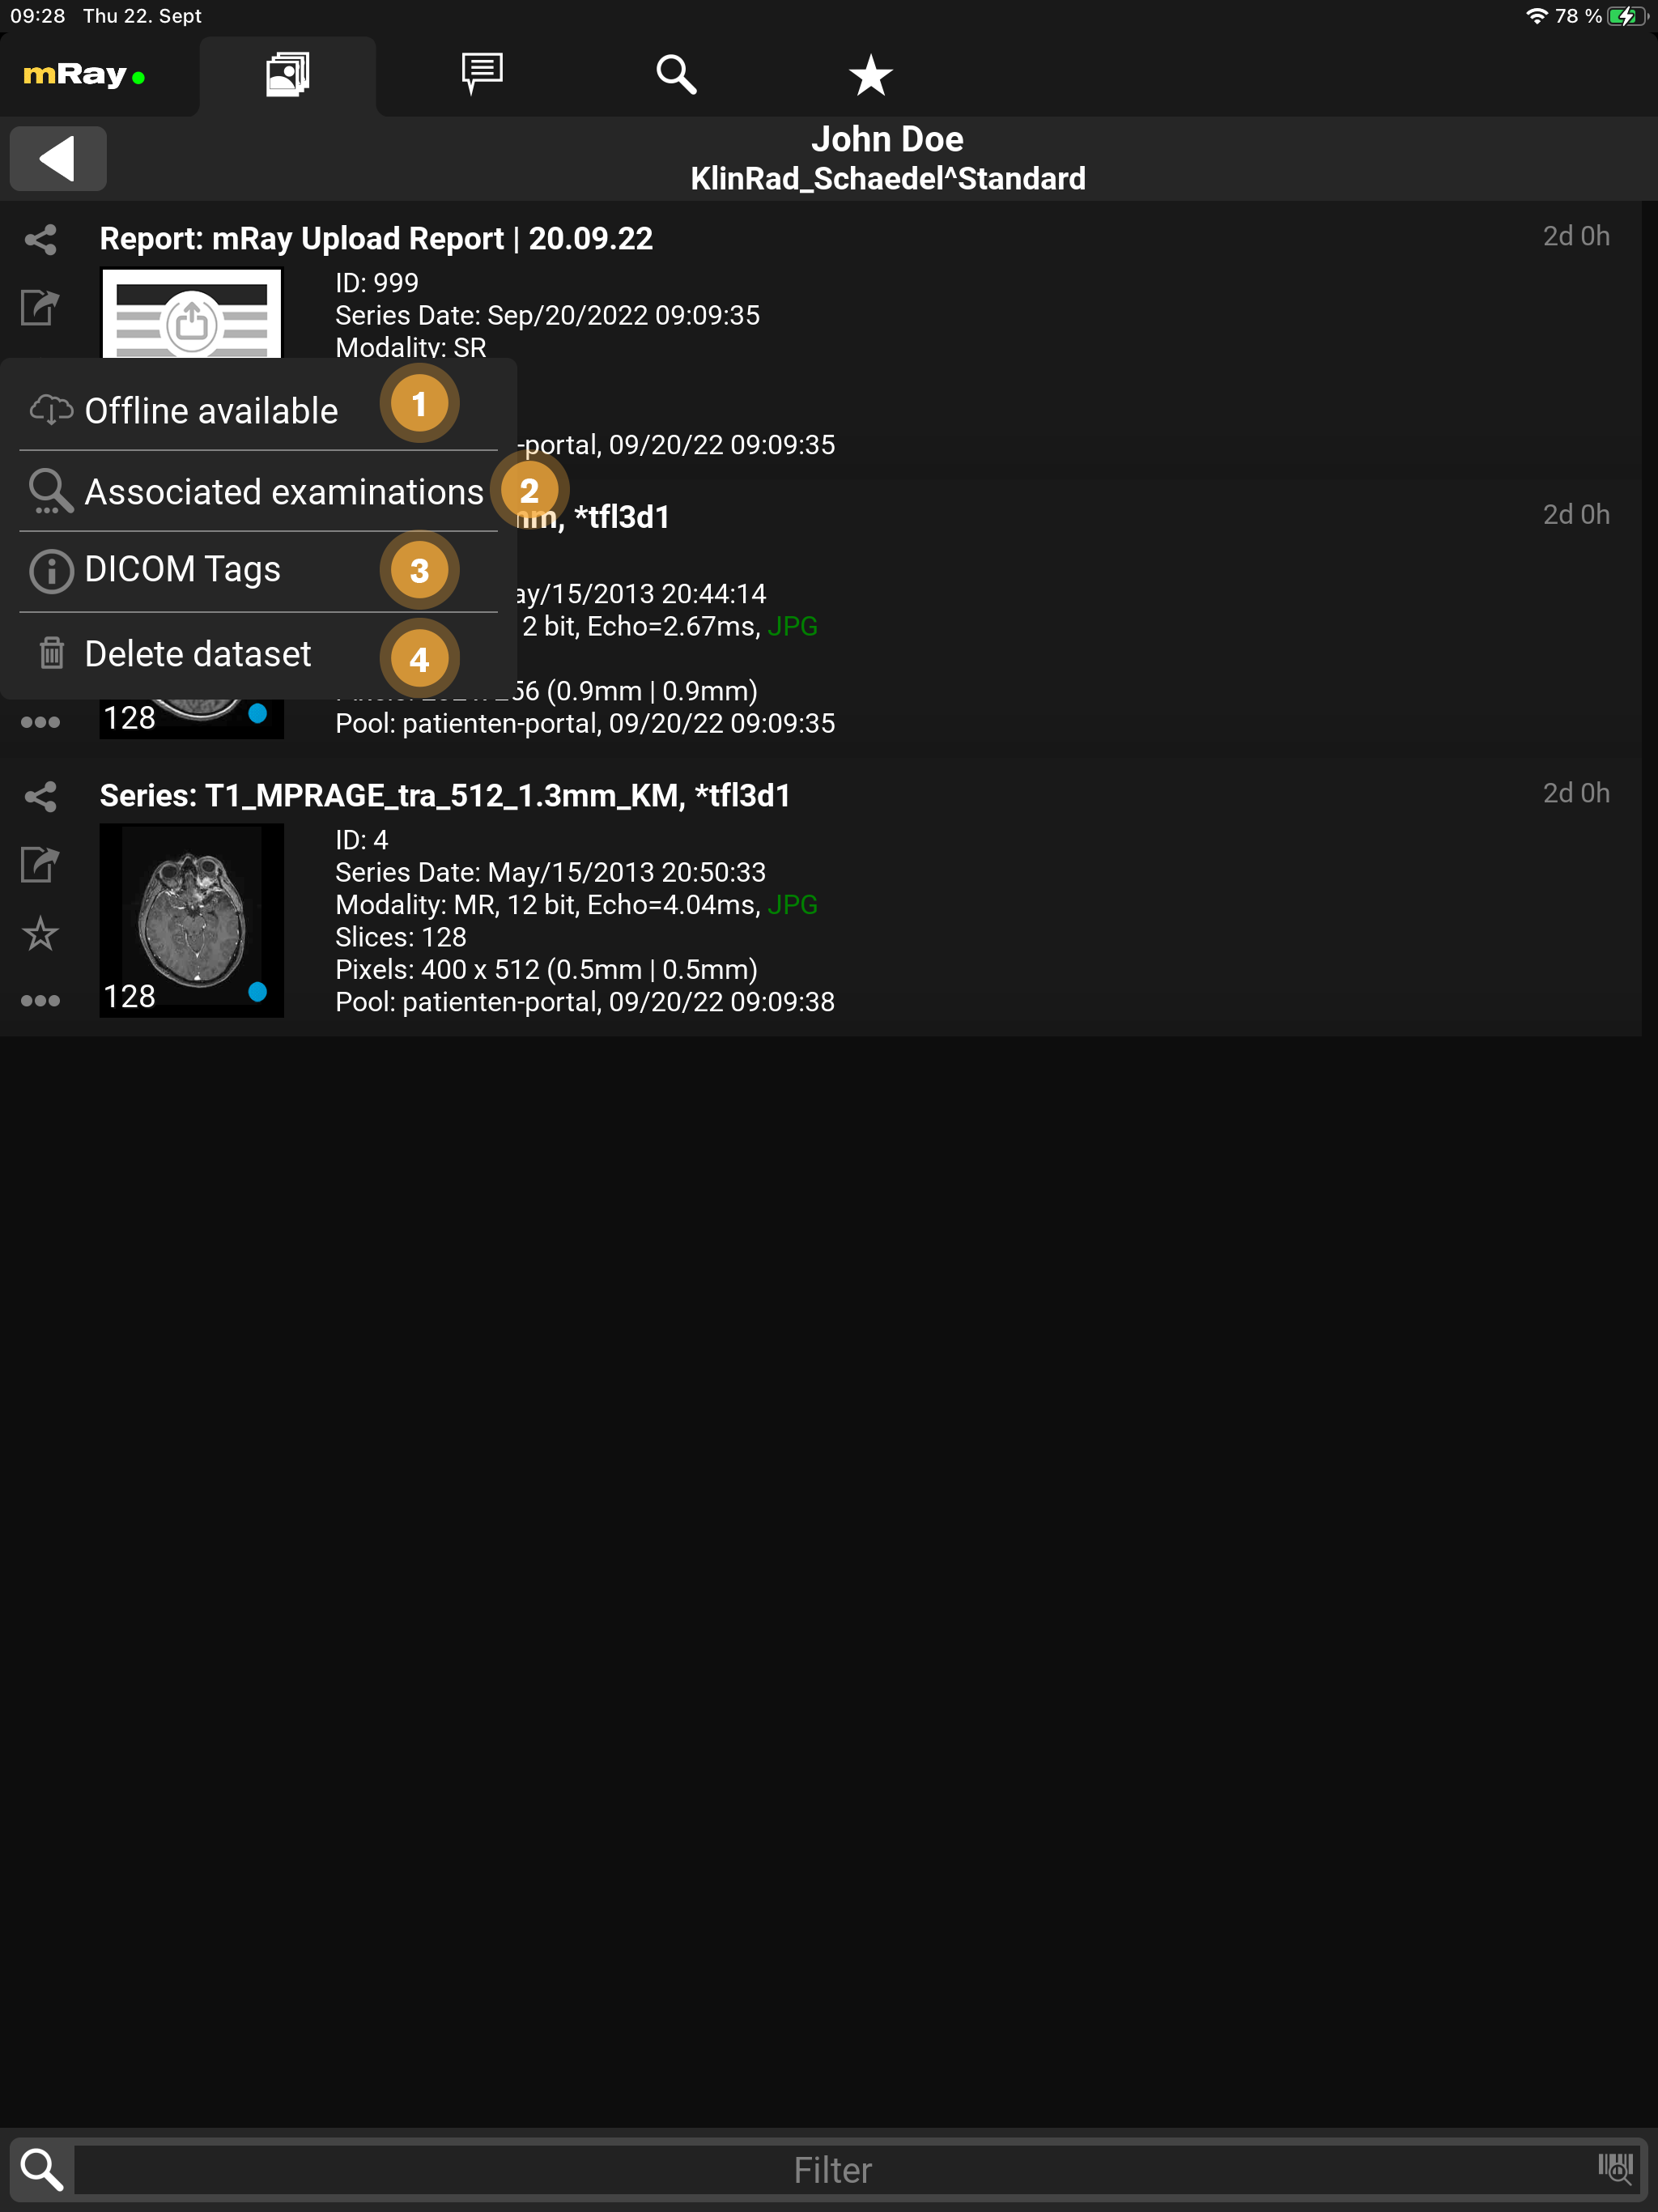

9.2.1. Context menu

From the Inbox, as well as from the Series selection it’s possible to execute more actions through the context menu.

-

Offline available: You can download the image data in mRay to have it available even if you are offline.

-

Associated examinations: Find associated studys to this patient.

-

DICOM-Tags: In case the current user has it enabled, it’s possible to view the DICOM tags of the series.

-

Delete dataset: In case the current user uploaded the dataset himself, he/she can delete them here again (from the server & client).